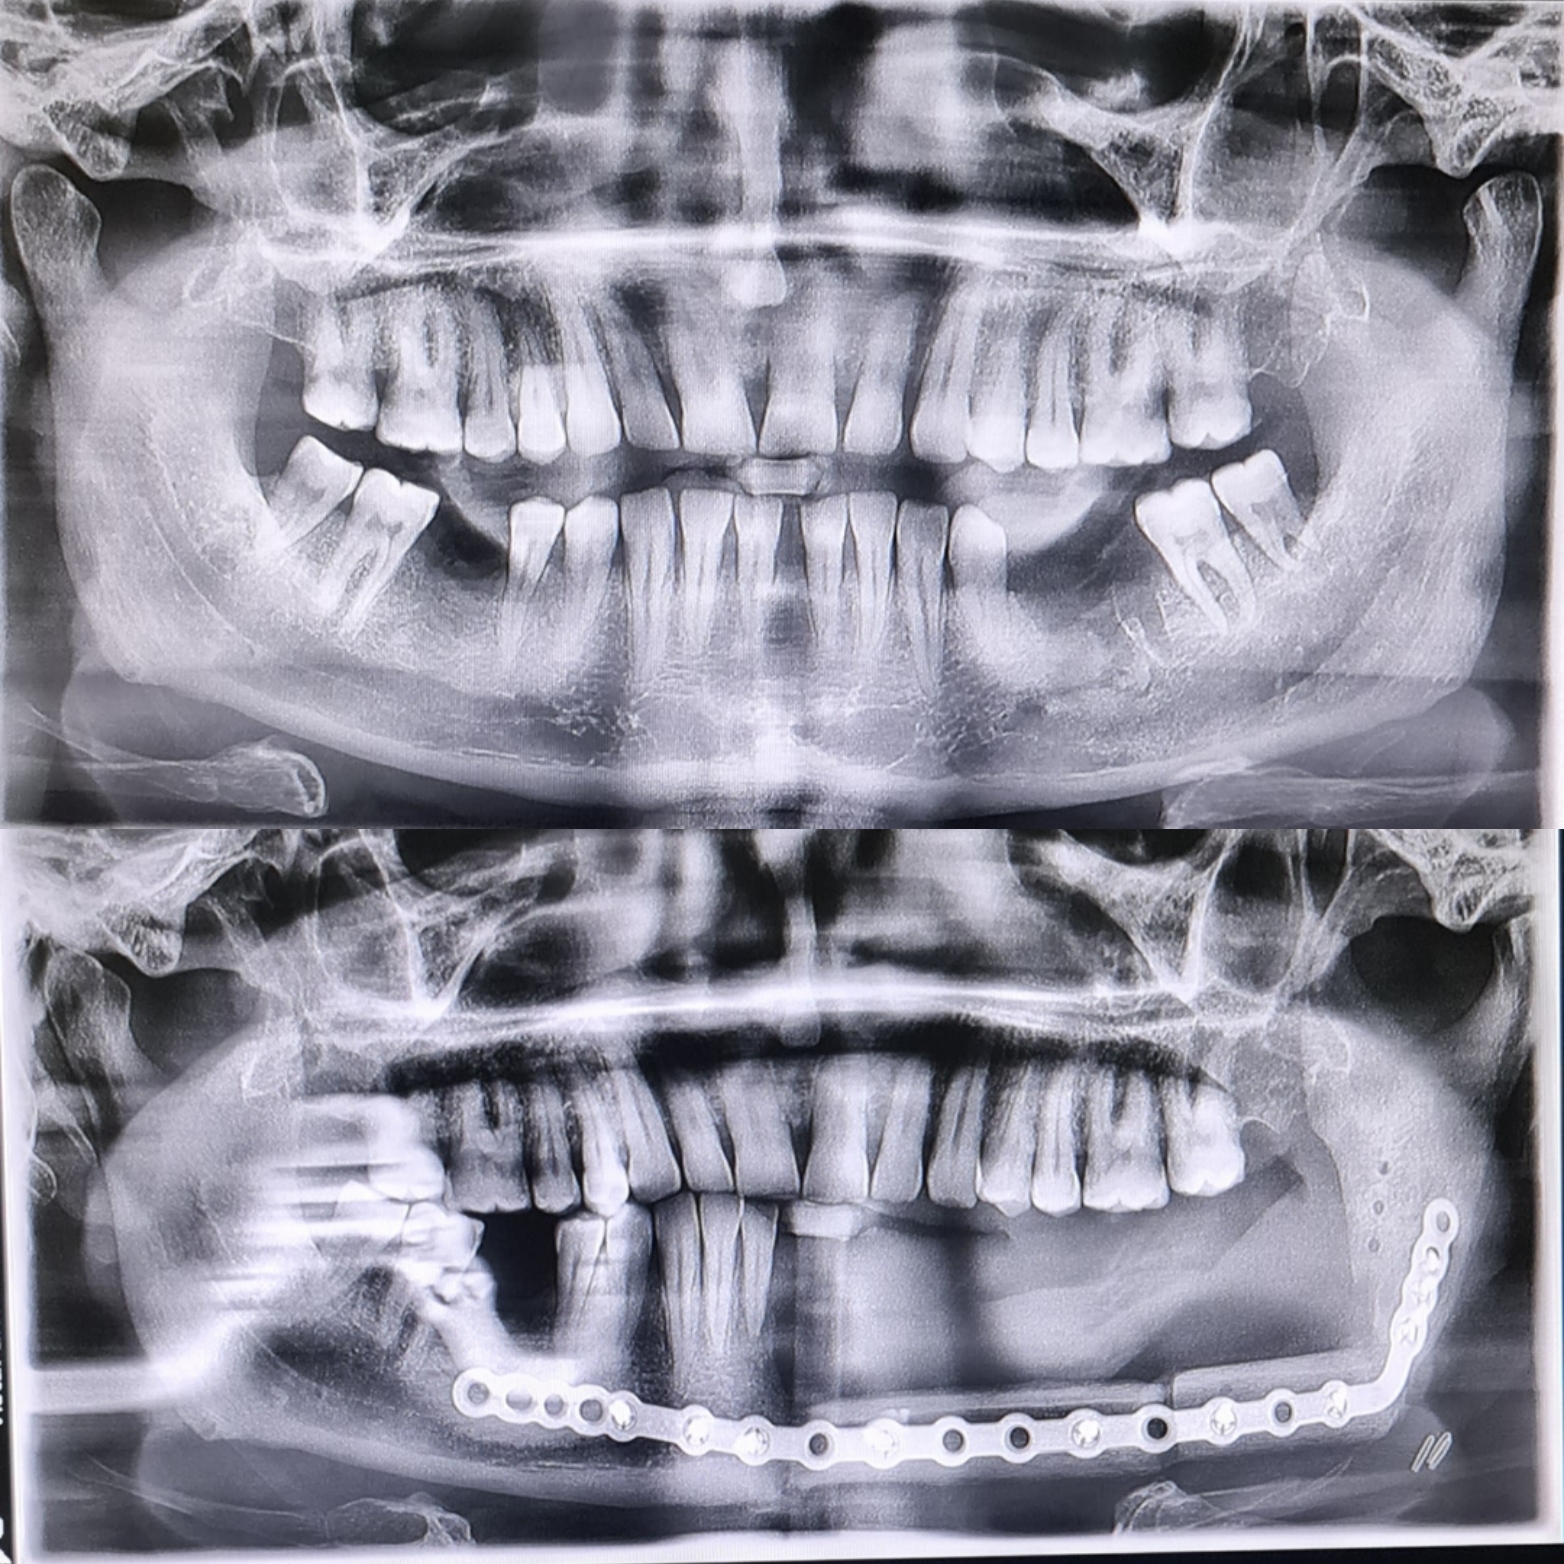

Bacaktan kemik nakli ile alt çene rekonstrüksiyonu